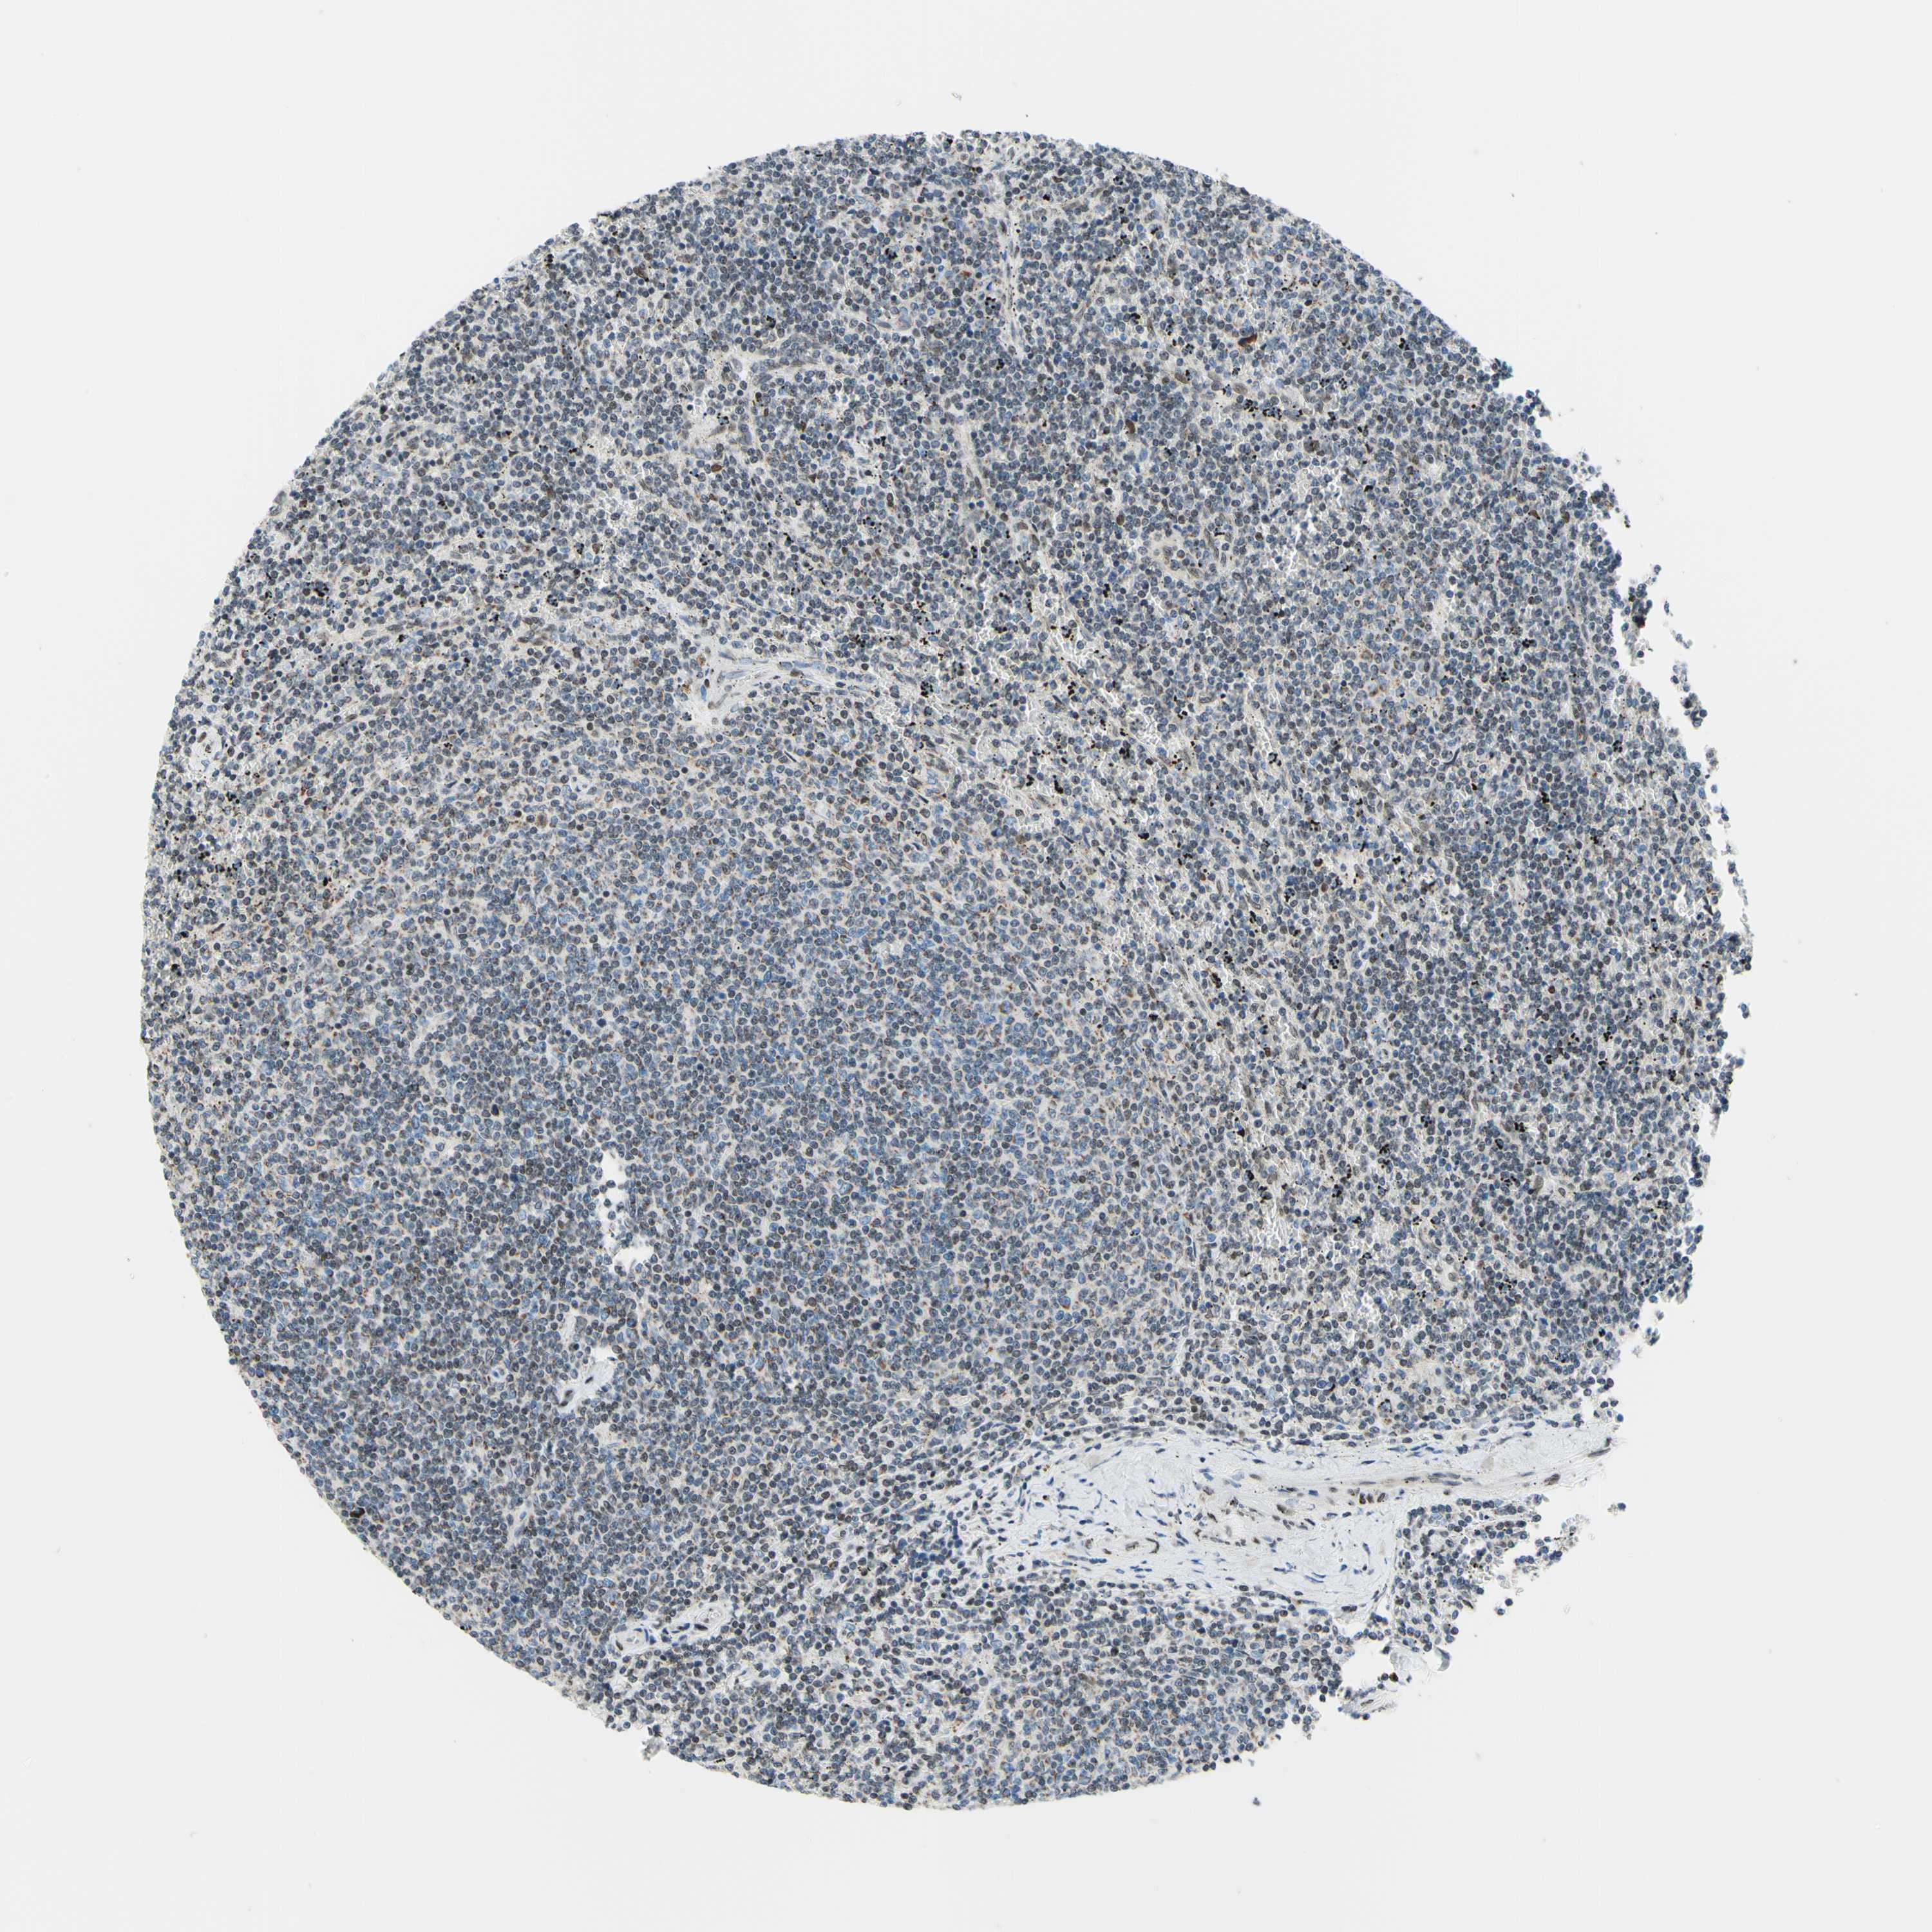

LYMPHOMA - Protein expressioni

A mouse-over function shows sample information and annotation data. Click on an image to view it in a full screen mode. Samples can be filtered based on level of antibody staining by selecting one or several of the following categories: high, medium, low and not detected. The assay and annotation is described here.

Each image is clickable and will lead to virtual microscopy that enables deeper exploration of all samples and also displays staining intensity scores, fraction scores and subcellular localization as well as patient and tissue information for each sample.

Antibody CAB011574

Staining

High

Medium

Low

Not detected

Intensity

Strong

Moderate

Weak

Negative

Quantity

>75%

75%-25%

<25%

None

Location

Nuclear

Cytoplasmic/membranous

Cytoplasmic/membranous,nuclear

Hodgkin's disease, NOS

Malignant lymphoma, non-Hodgkin's type, High grade

Malignant lymphoma, non-Hodgkin's type, Low grade